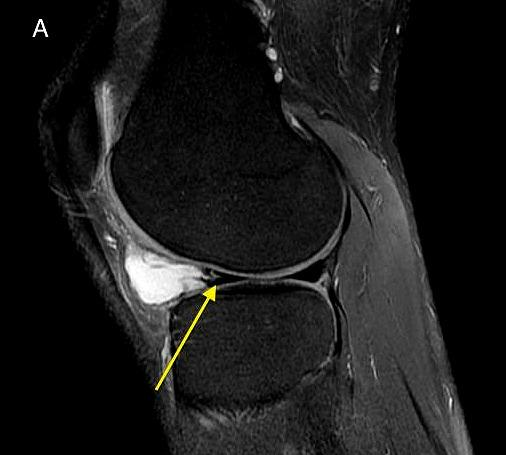

膝关节前交叉韧带囊肿1例

图片尺寸750x663